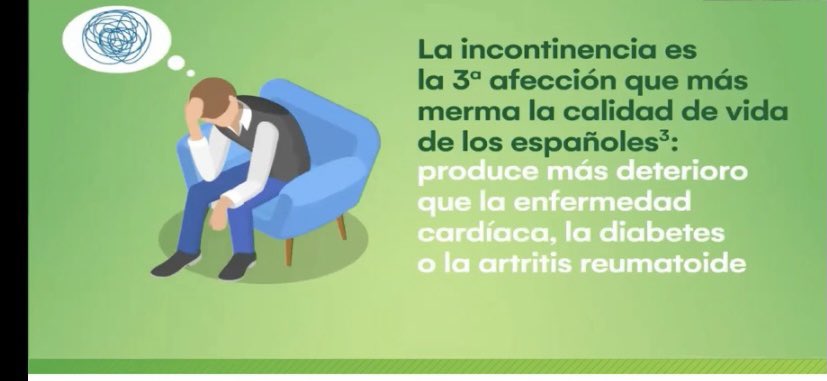

#incontinencia365dias la #incontinencia es la tercera afección que más merma en la #calidad de vida de los #españoles … porqué tardamos tanto a llegar al #especialista ? AECP SINUG Medtronic España Coloplast Incontinencia España Biocablan S.L Wellspect Iberia WFIPP aecirujanos